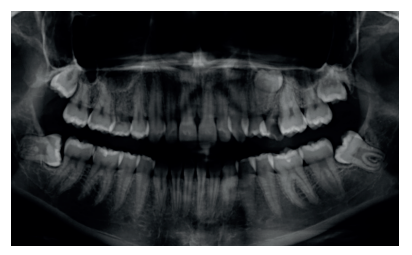

Caso clínico: se presenta un caso clínico de una mujer de 20 años, sin antecedentes médico-quirúrgicos de interés, que acudió a consulta remitida por su ortodoncista, para la extracción de un premolar maxilar retenido, en posición invertida. Tras la extracción del premolar y del tercer molar inferior retenidos, se obtuvo dentina procedente de ambos, para la regeneración ósea guiada del defecto resultante de la extracción del premolar, realizando revisiones a la semana y a los 4 meses de la intervención.

Clinical case: a clinical case of a 20-year-old woman is presented, with no interesting medical record, who went to dental clinic for removal of an inverse maxillary bicuspid retained. After maxillary bicuspid and lower third molar extractions, autogenous dentin was obtained from both teeth, to perform a guided bone regeneration of the bicuspid defect. A week and 4-month check-up were carried out.

El objetivo de este caso clínico es presentar la eficacia de la dentina autógena como material de injerto en un procedimiento de ROG, tras la exodoncia de un premolar superior izquierdo retenido, en posición invertida.